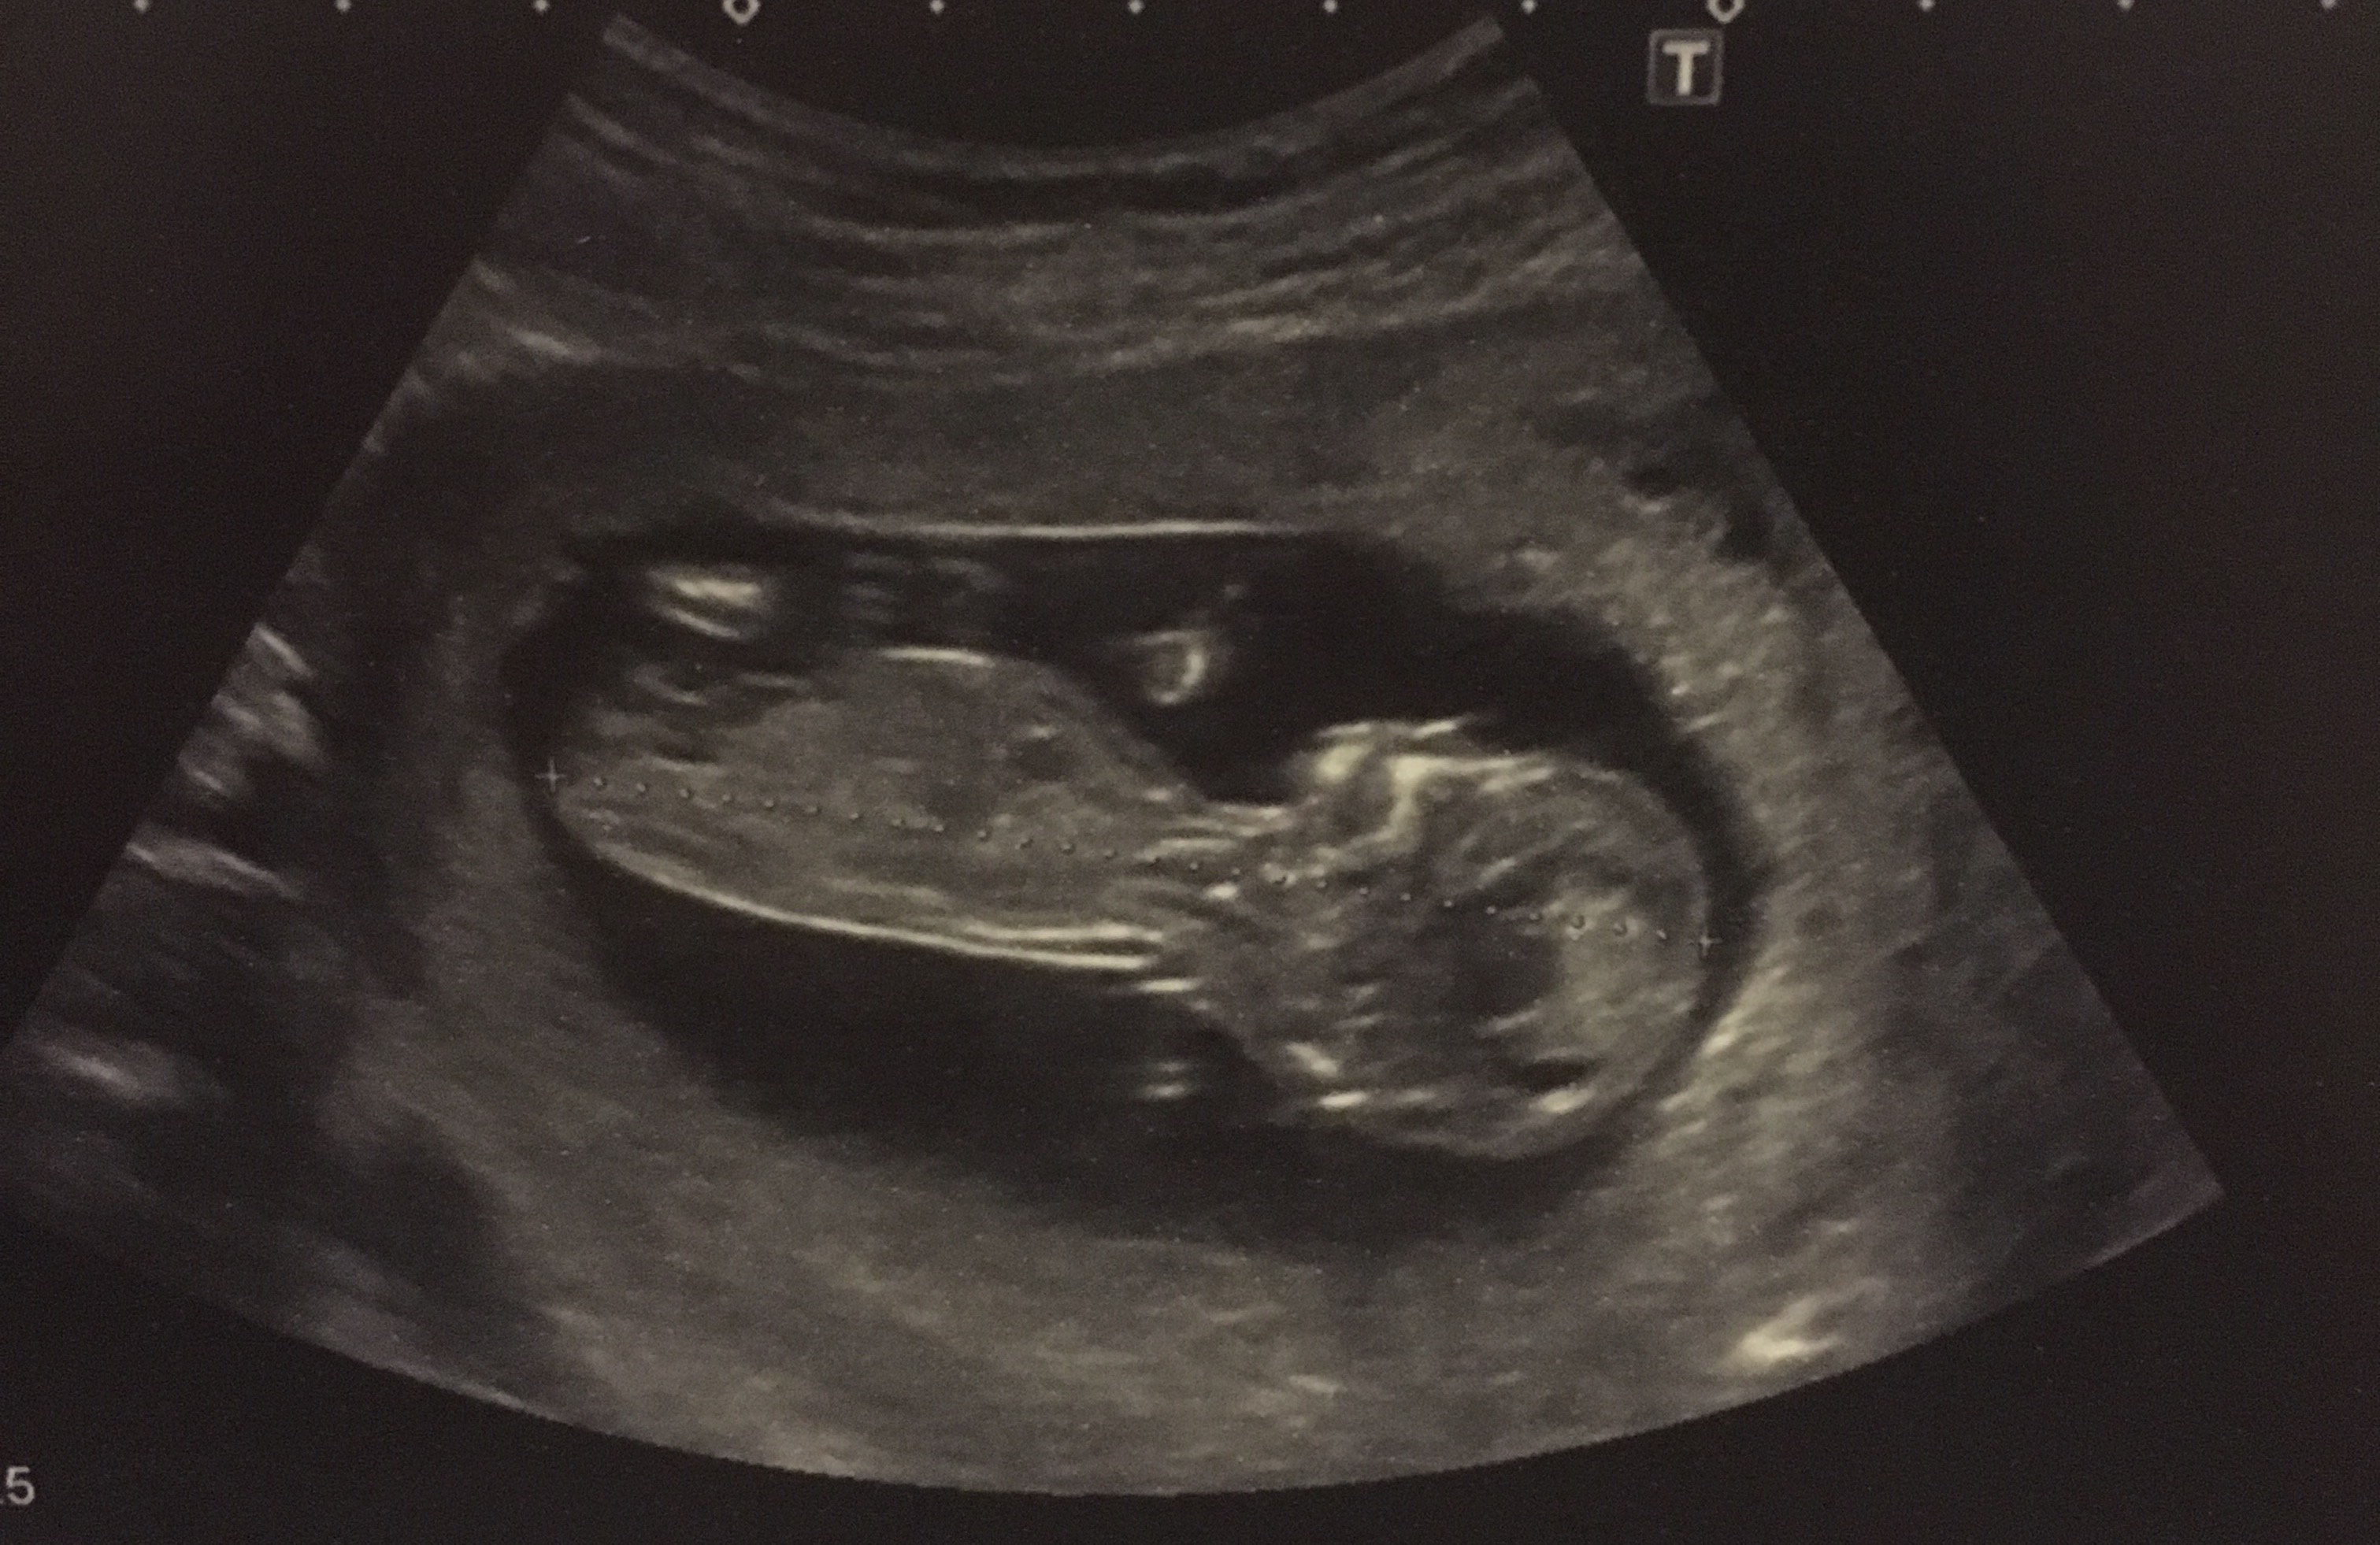

12 wks 5 days